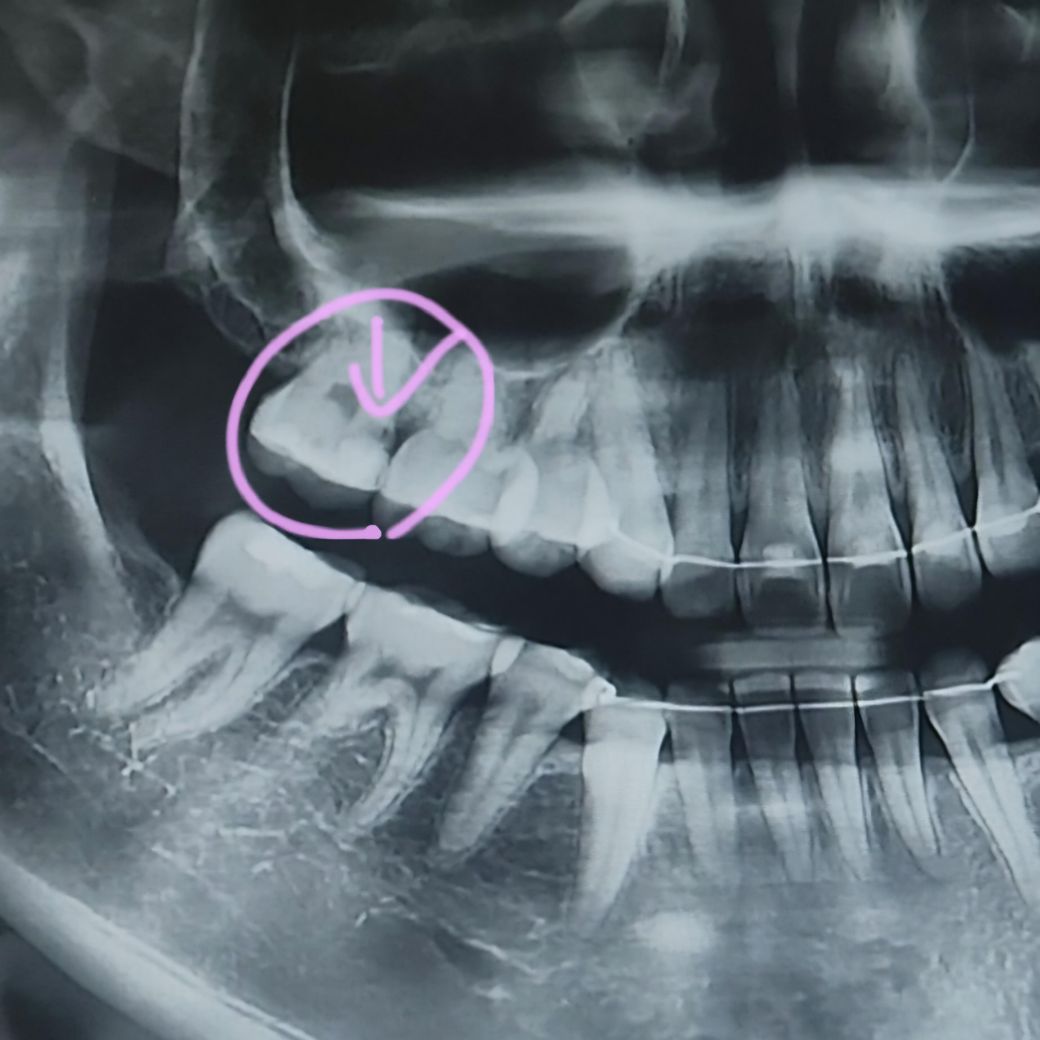

표시한 부분에 충치가 있다고 하셨는데 정도가 어떤가요?ㅠㅠ

그리고 어떤 치료를 받아야 하나요?

기존에 떼웠던 수복물을 제거해보고 충치 정도를 봐야할 것 같습니다 옆면이기 때문에 인레이로 떼울 것 같습니다

이전에 충전한 충전물 하방으로 충치가 있는것으로 보입니다.

이런경우 충전물을 제거하고 충치를 제거해야 하며 경우에 따라서는 신겨치료가 필요할 수 있습니다.

또함 치아의 많은 부분이 상실되었다면 크라운 치료가 필요할 수 있습니다.

치아의 옆부분에 충치가 생긴경우 신경과 거리가 가깝기 떄문에 신경치료를 해야될 가능성도 있어 보입니다.

충치의 정도는 꽤 많이 진행된 편이며 신경치료 및 크라운치료를 해야할 가능성이 높아보입니다.